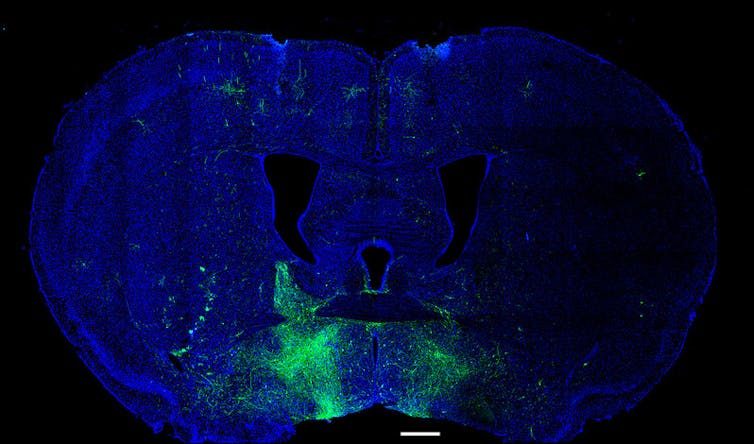

Para isso, codificamos geneticamente biossensores nos neurônios de camundongos que se iluminariam em resposta à atividade sináptica e neural. Monitoramos essa atividade em tempo real à medida que os camundongos aprendiam uma tarefa que envolvia pressionar uma alavanca em uma determinada posição após uma sugestão sonora para receber água.